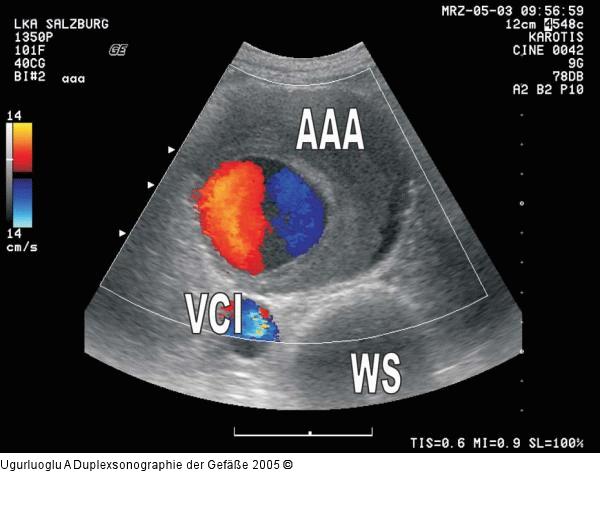

Abbildung 2: Duplexsonographie - Aneurysma Infrarenales Aortenaneurysma (AAA) mit einer exzentrischen Thrombusmanschette ventral der Vena cava inferior (VCI) und der Wirbelsäule (WS) |

Abbildung 2: Duplexsonographie - Aneurysma

Infrarenales Aortenaneurysma (AAA) mit einer exzentrischen Thrombusmanschette ventral der Vena cava inferior (VCI) und der Wirbelsäule (WS) |